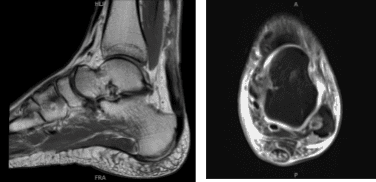

MRI was reviewed that showed full-thickness achilles tendon tear at the myotendinous junction 6 cm from the calcaneal insertion with a 4 cm gap retracted tendon stumps. Complete tear of the anterior talofibular ligament and calcaneofibular ligament. Diffuse lateral and posterior soft tissue edema.

MRI Left ankle non-contrast